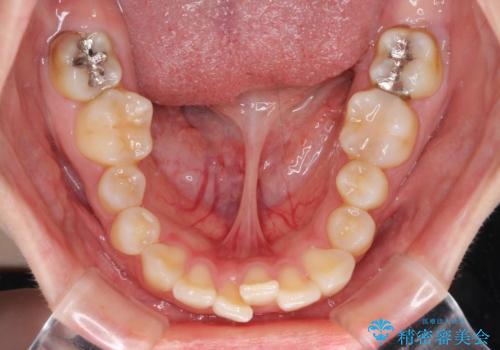

下顎前歯が隠れて突出した口元 ワイヤー装置での抜歯矯正

- 前歯のデコボコと口元の突出感を気にして来院された患者様です。

下顎骨の左右差や、上顎骨の前方位などが認められたため、上下左右の第1小臼歯4本を抜歯し、ワイヤー装置にて矯正治療を行うこととしました。